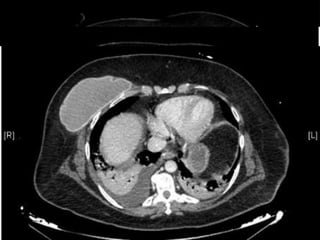

◦ TC Tórax:

EVOLUCIÓN INICIAL UMI 17/02/2014: ◦ IOT ◦ FBC: restos hemáticos en el interior del tubo y árbol bronquial ◦ Estudio autoinmune:  Ig y complemento normales  ANAs y ENAs negativos  P-ANCA positivo título 1/320 (MPO > 134’0 U/ml)  Ac anti-MBG + Ac SAF negativos  Anti-DNAds 12’5  VSG 141 mm  Ac antiperoxidasa 1720’6 UI7ml ◦ Serologías:  VHB, VHC, VIH, Sífilis  negativos  VHS, VVZ, CMV, parvovirus  negativos  18/02/2014: ◦ Ecocardiograma:  VI con masa ligeramente aumentada + FE 55%  No datos indirectos de aumento de PAP ◦ TC Tórax:

 TC  descarta origen neoplásico